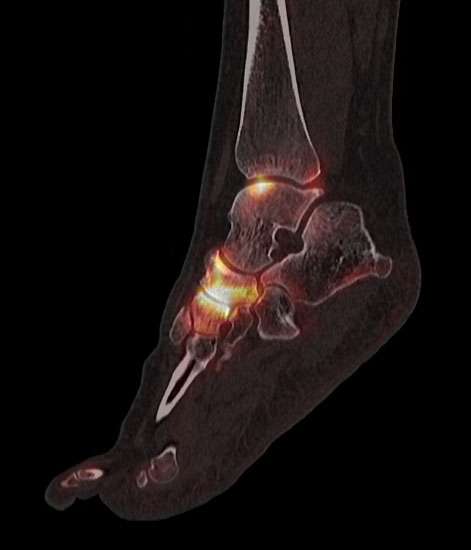

Die Kombination von SPECT und CT in einem Untersuchungsgang bringt wie bereits oben erwähnt eine erhöhte Ortsauflösung und artefaktfreie Darstellung von Knochenstoffwechselveränderungen der SPECT bei gleichzeitig excellent guter anatomischer Darstellung/Zuordnung durch die CT 3. Auf die Vorteile der CT gegenüber dem konventionellen Röntgen muss nicht mehr besonders eingegangen werden. Besonders eignet sich die „SPECT-CT“ zur Diagnostik von Fußerkrankungen (Biersack HJ et al. 2012).

Aufgrund der optimalen funktionellen Darstellung (PET) und der entsprechend guten anatomischen Bildgebung kann dieses kombinierte Untersuchungsverfahren viele Fragestellungen auch im Bereich des Fußes beantworten. Exemplarisch werden folgende Indikationen erwähnt. Abklärung von Infektionen im muskuloskelettalen Bereich 45, Untersuchungen von unklaren Fußschmerzen (Biersack HJ et al. 2012), präoperative Bildgebung beim Charcot-Fuß/diabetischer Fuß 31.